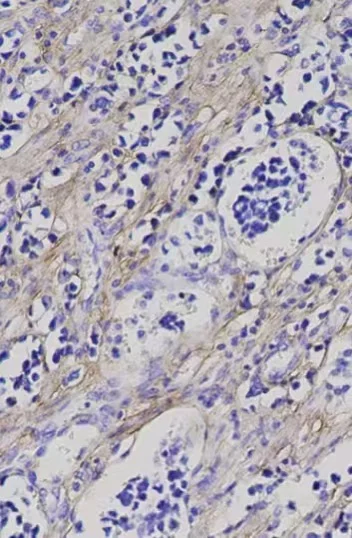

使用适当的显色剂(如DAB)使抗原-抗体复合物显色

使用苏木素等染料对细胞核进行复染,以便在显微镜下更好地观察组织结构

观察:将封好的切片放在显微镜下观察,记录实验结果。#医学生 #医生评职称 #动物实验外包 #细胞实验 #医学生#医生